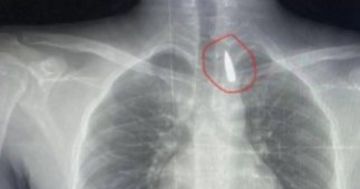

السوسنة - في إنجاز طبي استثنائي، نجح فريق طبي مصري من مستشفيات جامعة الإسكندرية في إنقاذ حياة مصاب فلسطيني من قطاع غزة، بعد إجراء عملية جراحية دقيقة لاستخراج مقذوف ناري استقر قرب الشريان الأورطي داخل تجويف القفص الصدري، في حالة وصفت بأنها بالغة الخطورة.

وأوضح الدكتور تامر عبد الله، عميد كلية الطب ورئيس مجلس إدارة المستشفيات الجامعية، أن العملية استغرقت عدة ساعات، وشارك فيها أطباء متخصصون في جراحة القلب والصدر والتخدير، وتم خلالها إزالة المقذوف بأمان، رغم قربه من أهم شرايين الجسم المسؤول عن تغذية الأعضاء الحيوية.